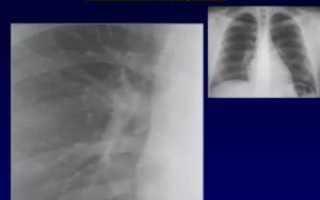

Флюорография лёгких, на данный момент, является основным механизмом массовой проверки населения на наличие туберкулёза.

Это объясняется дешевизной и простотой метода, хотя он и не гарантирует стопроцентных результатов.

За счёт этого исследования можно обнаружить изменения в тканях, например, их плотность и развитие каких-либо опухолей или полостей с жидкостью

Важно! Рентгенограмма позволяет определять не только заболевания лёгких, но и костей. В частности, можно обнаружить сколиоз, травмы рёбер, а в некоторых случаях и поражения диафрагмы.

Например, сильно поднятая диафрагма может означать избыток газов в брюшине, что бывает одним из признаков перитонита.

В первую очередь врачи обращают внимание на корни лёгких — структуры, которые являются так называемыми воротами в лёгкие.

В норме на рентгенограмме они не увеличены, на их фоне не видны никакие образования. Само расположение корней также имеет значение.

Корни делят на три сектора — верхний, средний и нижний. Правый корень напоминает искривлённую ленту, которая средне выражена и сужается книзу.

Верхняя часть этого корня расположена на том же уровне, что и передний отрезок второго ребра — второго межрёберья. Верхняя часть левого корня расположена на одно ребро выше правого, а сам он частично скрыт тенью от сердца.

Важно! В некоторых случаях картина может отличаться от нормы, притом что сам пациент чувствует себя хорошо.

Это может происходить из-за особенностей развития организма пациента либо из-за происходивших ранее операций или травм.

В редких случаях это говорит о некачественно сделанном снимке, когда пациент пошевелился или же изначально стоял в неправильной позе.

Имеет значение жёсткость и мягкость снимка — в первом случае глубина изображения будет слишком велика, что не позволяет увидеть мелкие детали, а во втором изображение будет слишком размыто.

Помимо ранее упомянутых новообразований, можно отметить следующие характеристики корней, которые обозначаются в письменных заключениях, являются отклонениями от нормы и могут быть признаками патологий: уплотненные, тяжистые и расширенные корни, также корни могут быть усилены.

Обычно это происходит из-за отёка бронхов или крупных сосудов. А в некоторых случаях и из-за того, что происходит увеличение лимфоузлов.

Уплотнение и расширение ткани корней почти всегда происходит одновременно, если же корни только уплотнены, это говорит о хроническом процессе.

На снимке расширенные корни будут выглядеть менее чёткими, а также крупнее стандартных размеров.

Этот термин означает, что в лёгких может происходить как острый, так и хронический процесс. Чаще всего это связывают с профессиональными заболеваниями (например, асбестоз) или с хроническими (например, бронхит курильщика).

На рентгенограмме тяжистые корни выглядят более плотными и неровными, это объясняется увеличением количества соединительной ткани — тяжей.